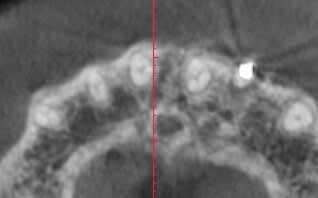

en regardant le CBCT, je me demande si l'on peut faire une ROG ( bio oss + biogide) lorsque comme ici, toute

la table externe semble lysée le long de la racine